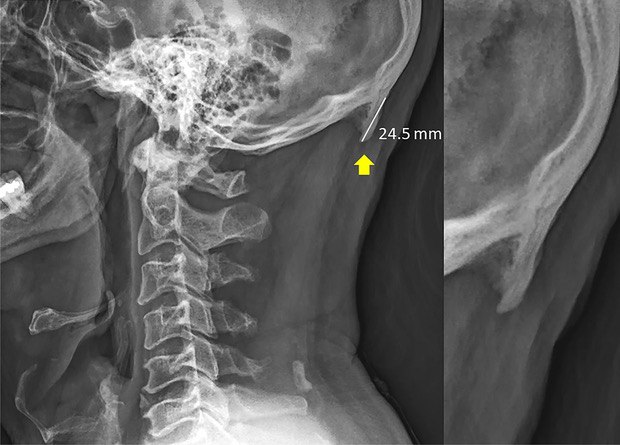

Полтора года назад австралийские ученые объявили, что нашли «смартфонную кость» — вырост на затылке, который особенно часто встречается у молодых людей. Сейчас они опубликовали правки к своей статье, из которых следует, что выборка была искажена и выводы оказались преждевременными. А еще у одного из авторов нашелся конфликт интересов: оказалось, что он занимается хиропрактикой и продает пациентам услуги по исправлению осанки